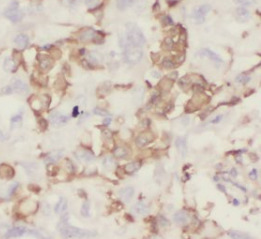

Immunohistochemical of paraffin-embedded human lung cancer using FNab08401(Surfactant protein D antibody) at dilution of 1:50 IP Result of anti-Surfactant protein D (IP:FNab08401, 3ug; Detection:FNab08401 1:300) with mouse lung tissue lysate 2800ug. |